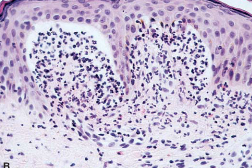

Darkly pigmented, variegated lesions distributed primarily on the trunk and non-sun-exposed skin. These moles feature a combination of architectural disorder (rete-to-rete bridging of melanocytes) and cytologic atypia (melanocytes with large atypical nuclei). These patients are at an increased risk of developing melanoma.

A

Dysplastic nevi

(image displays bridging of rete ridges and melanocytes with cytological atypia, curved arrows)